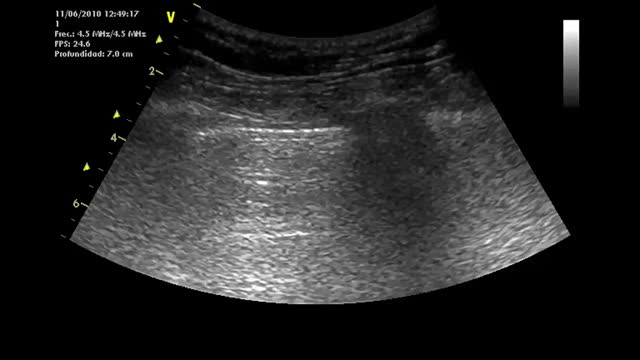

Displacement or excursionThe measurement of displacement assesses the capacity of the diaphragm to generate volume changes in the thorax.29,31 The patient is placed in the supine position with the trunk raised 30º, and the hemidiaphragm is studied in 2D mode. For this purpose we adopt a subcostal approach, using a low-frequency convex probe at the mid-clavicular line, seeking the posterior third of the diaphragmatic dome on the right side, through the hepatic window (the probe is placed between the mid-clavicular line and the anterior axillary line, directing it medial, cranial and dorsal so that the ultrasound beam reaches the posterior third of the diaphragm)(Suppl. Fig. 9).22,26,28,30 On the left side, we use the splenic window, but the dome is more difficult to locate, generally due to the interposition of the abdominal organs (Suppl. Fig. 10). In order to obtain the best possible image, we place the probe in the inferior intercostal or subcostal zone between the mid-axillary and anterior axillary lines, or at the mid-clavicular level. The probe is displaced in a way similar to the right side to also visualize the posterior third. An alternative is to use the lateral approach, placing the probe perpendicular to the inferior intercostal spaces at the level of the mid-axillary line (Suppl. Fig. 10).22

After locating the dome in 2D mode, the M mode allows us to identify the portion of the dome with the greatest motility, measuring it in a sagittal view. On both sides, we observe a curved hyperechogenic line corresponding to the diaphragm (Suppl. Fig. 11). A curve reflecting the respiratory cycle is seen in which the upper part corresponds to the inspiratory phase (during inspiration, diaphragm motion is caudad and the line moves towards the probe) and the lower part to the expiratory phase (displacement is cranial and the line moves away from the probe)(Suppl. Fig. 11).30–32

In general, we interpret respiratory cycles corresponding to slow and deep breathing in patients under spontaneous breathing conditions, though measurement can also be made during nasal “sniffing” effort (little used in the ICU). In practical terms, we measure displacement in breathing under resting conditions (Suppl. Fig. 13) and in deep inspiration and expiration (Suppl. Figs. 11 and 12).

We trace a vertical line with the first calibrator at the base of the inspiratory curve, corresponding to the end of normal expiration, and with the second calibrator we focus on the peak of the inspiratory curve. The mean of the measurement of three or more cycles, or the highest value of 5 cycles, is recorded.